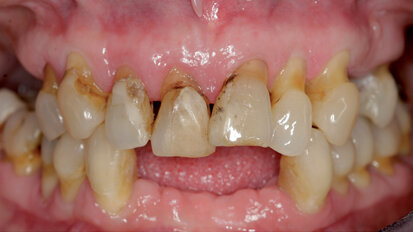

Management kosti a měkkých tkání při komplexní rekonstrukci jednoho zubu implantátem

Rekonstrukce jednoho frontálního zubu implantátem bývá pravděpodobně největší estetickou výzvou pro praktického zubního lékaře. Správné ...